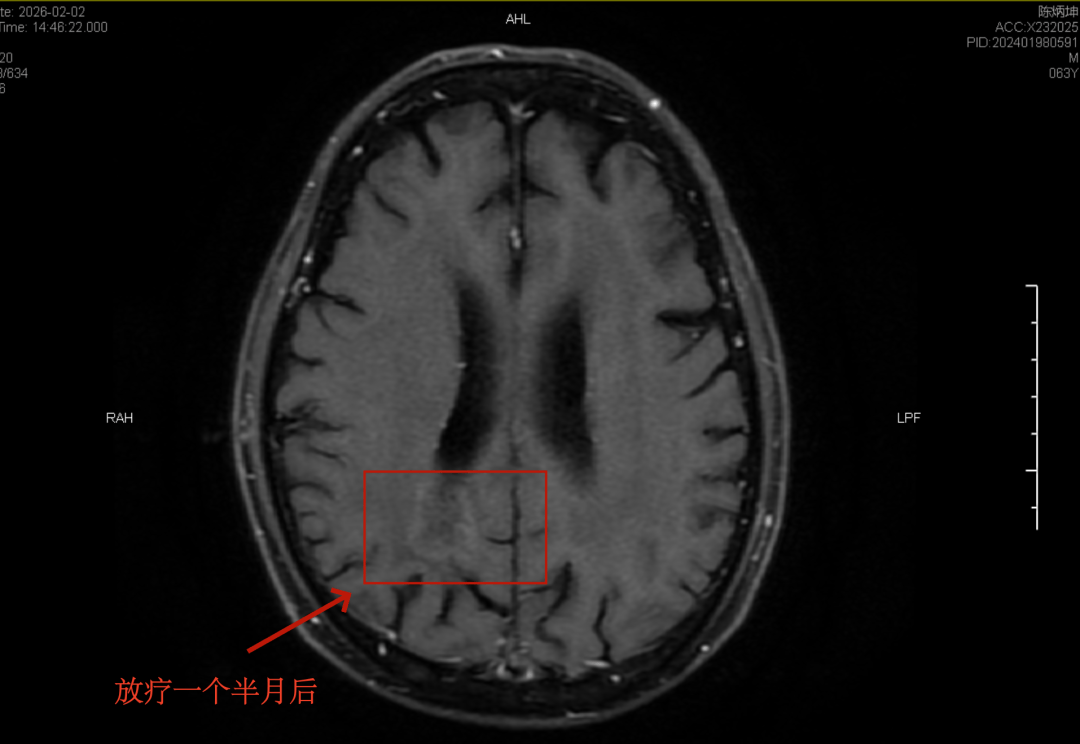

放疗一个半月后复查的头颅核磁共振结果也让朱先生一家十分欣慰:肿块周围的水肿基本消退,原先在黑色底片上触目惊心的白色肿瘤灶也只剩下一点极浅的痕迹。